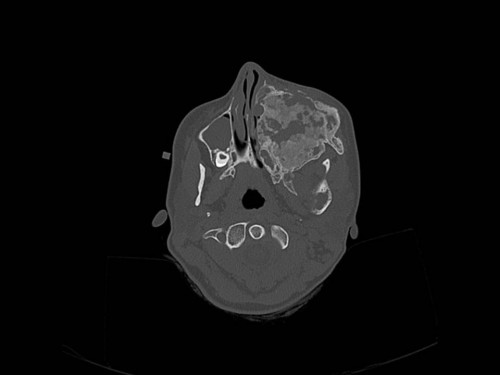

Eine 16-jährige Patientin kommt in eine MKG-chirurgische Praxis zur Abklärung der weiteren Vorgehensweise bzgl. ihrer Erkrankung.

Sie betrachten die angefertigten Röntgenbilder. Welche der folgenden Röntgenbefunde ist korrekt? Ossäre Auftreibungen im Bereich …

- A… der Mandibula links.

- B… des Os frontale links.

- C… des Os zygomaticum links.

- D… des Os temporale links.

- EAlle genannten Aussagen sind korrekt.

Bildgebung - OPAN 2004